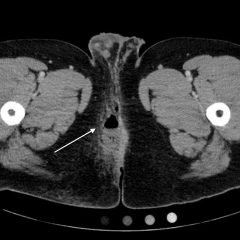

A 57-year-old male with a history of intravenous drug use presented to the emergency department with four days of progressively worsening pain and swelling to his left buttock after injecting heroin subcutaneously (i.e., “skin popping”). Labs were significant for a white blood cell count (WBC) of 26.7×103/mm3. Using the high frequency, linear probe, a point-of-care ultrasound (POCUS) was performed and revealed a large soft tissue abscess.

The patient in this case was given broad spectrum antibiotics and went to the operating room later that day with general surgery due to the high degree of muscular involvement and the size of the abscess cavity. Over 200 mL of purulent fluid was drained from a pocket that measured 8x14x7cm.